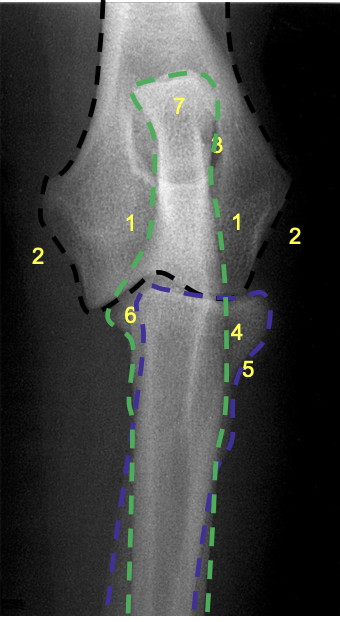

what is 8?

olecranon process of the ulna

what is 7?

olecranon of ulna

what is 1?

condyles of humerus

what is 2?

epicondyles of humerus

what is the red X marking?

anconeal process of the ulna

how does the olecranon process extend on a lateral view?

caudo-proximally

what is the relation of the medial condyle to the lateral condyle on a medio-lateral view of the elbow in a dog?

medial condyle is distal to the lateral condyle

where in the ulna is there a slight increase in opacity?

at the proximal extremity of the medullary cavity

where is the caudal ulnar cortex thicker?

in the proximal third of the diaphysis

what is the arrow at 8 pointing to?

physeal scar on distal physis of the radius